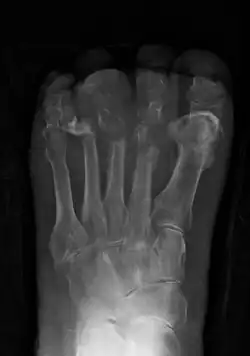

Osteomyelitis of the 1st toe

Extensive osteomyelitis of the forefoot